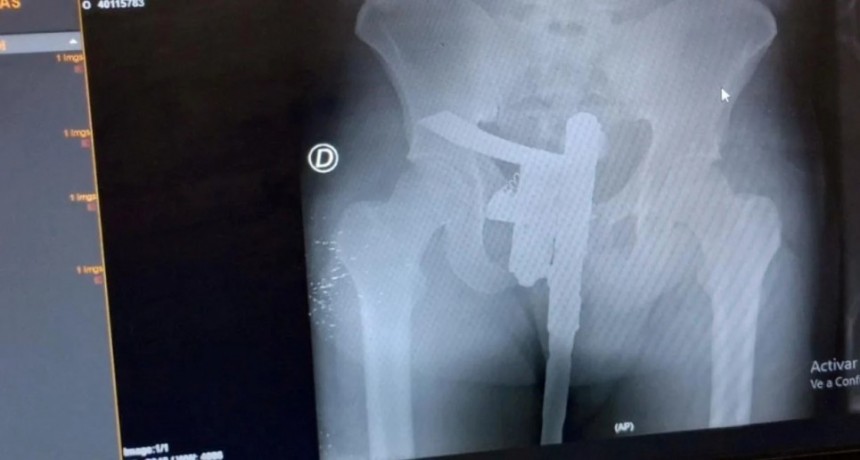

Radiografía con sorpresa: buscaban una fractura y encontraron un arma de fuego

Las situaciones críticas son algo habitual para el personal de salud (médicos y enfermeras). Pero lo que pasó la mañana del domingo en el hospital Cullen supera todos las marcas.